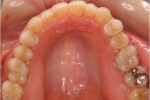

カテゴリー:開咬(overbiteがマイナスのもの)

| 治療中